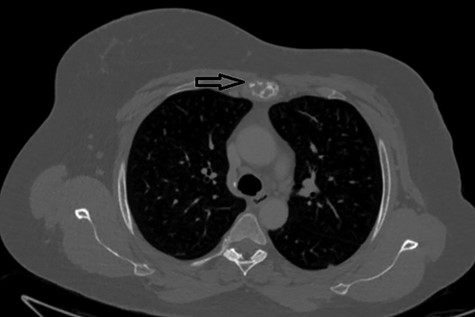

The second case at our institution was a 52-year-old woman with a history of left breast carcinoma treated for which she had undergone left wide local excision and sentinel node biopsy. Due to uncertainty regarding margins, she required a re-resection of her left breast tissue. She completed adjuvant radiotherapy and received maintenance hormonal therapy. She presented 8 months following her radiotherapy with sternal pain and positron emission tomography–computed tomography (PET–CT) imaging demonstrated localized uptake within the sternum (Fig. 3). Biopsy demonstrated proven recurrence of metastatic breast cancer. She was seen in clinic and counselled for partial sternectomy and reconstruction. She underwent partial sternectomy and underwent reconstruction with Synthes® plates. Her post-operative recovery was unremarkable. Post-operative histology was consistent with metastatic breast carcinoma, which was completely excised. The patient made an uncomplicated recovery and was seen in the outpatient clinic with a satisfactory post-operative chest radiograph (Fig. 4).

CT–PET demonstrating increased metabolic activity within the sternal lesion.